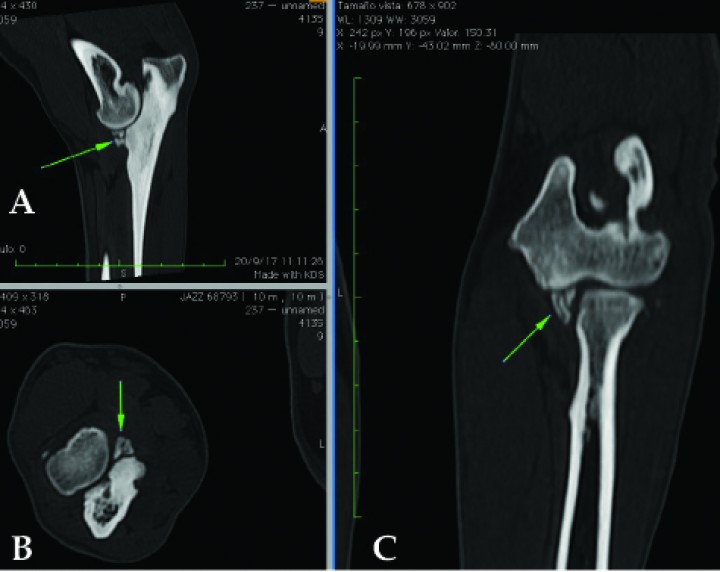

Es por todo ello que en los casos dudosos la radiología puede que no sea suficiente y se requiera la realización de una tomografía, como ocurrió en un 18% de los casos del presente trabajo. Mediante esta técnica, la localización, el número y el tamaño de los fragmentos coronoideos, así como la presencia de lesiones osteocondrales, es mucho más precisa. Sin embargo, el diagnóstico por tomografía no está exento de algunos problemas. Un estudio comparando la utilidad de la artroscopia y la tomografía en el diagnóstico del EPCM[ Moores AP, Benigni I, Lamb CR. CT versus arthroscopy for elbow dysplasia lesions. Vet Surg 2008, 37, 390-398. [PubMed] ] mostró que la tomografía detectaba perfectamente los procesos coronoides cuando estaban fragmentados y desplazados (Fig. 7), pero con frecuencia no los detectaba cuando no había desplazamiento o las fisuras solo existían en el cartílago pero no en el hueso subcondral. Esto supone un problema porque en muchas ocasiones se pueden producir falsos negativos. A este respecto, es interesante un trabajo que cifra la detección de fragmentos por medio de la tomografía en el 18% de codos con fragmentos no desplazados observados artroscópicamente y en el 29% de codos con simples fisuras en cartílago observadas artroscópicamente.[ Groth AM, Benigni L, Moores AP, Lamb CR. Spectrum of computed tomographic findings in 58 canine elbows with fragmentation of the medial coronoid process. J Small Anim Pract. 2009;50(1):15-22. [PubMed] ] Todas ellas, en cambio, fueron detectadas con artroscopia. Otro hándicap de la tomografía es que los osteofitos en formación pueden erróneamente tomarse por pequeños fragmentos de coronoides, dando lugar a falsos positivos en un número no despreciable de casos. De igual manera, pequeños fragmentos calcificados en la tomografía muchas veces no se corresponden con hallazgos artroscópicos.[ Coppieters E, Van Ryssen B, van Bree H, et al. Computed tomographic findings in canine elbows arthroscopically diagnosed with erosion of the medial compartment: an analytical method comparison study. Vet Surg. 2015;44(4):511-20. [PubMed] ] En nuestra serie de casos, cuando se utilizó la tomografía solamente ocurrieron falsos positivos y falsos negativos en 11 codos (3%).

<p>Imágenes de tomografía computarizada en ventana de hueso de un Labrador de 10 meses. (<strong>A</strong>) Plano sagital. (<strong>B</strong>) Plano transversal. (<strong>C</strong>) Plano dorsal. Se observa la fragmentación del proceso coronoides (flechas verdes). Imágenes cedidas por el Departamento de diagnóstico por imagen del Hospital Universitario de Lugo.</p>

Figura 7

Imágenes de tomografía computarizada en ventana de hueso de un Labrador de 10 meses. (A) Plano sagital. (B) Plano transversal. (C) Plano dorsal. Se observa la fragmentación del proceso coronoides (flechas verdes). Imágenes cedidas por el Departamento de diagnóstico por imagen del Hospital Universitario de Lugo.